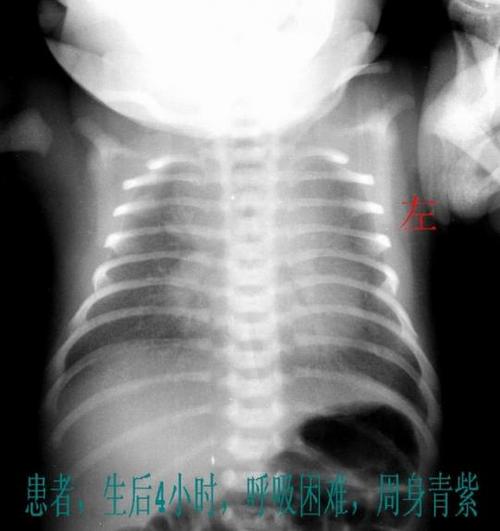

新生儿肺透明膜病(也叫新生儿呼吸窘迫综合征,NRDS)发生后的第3天,是病情的“分水岭”。

- 病情最重期已过:出生后24-72小时是NRDS病情最严重的阶段,在此期间,患儿呼吸困难最明显,对呼吸机的依赖性最强,并发症风险最高。

- 出生后6-24小时:随着呼吸开始,缺乏表面活性物质的肺泡大量塌陷,导致肺不张、气体交换困难,出现进行性加重的呼吸困难,这就是病情最重的时候。